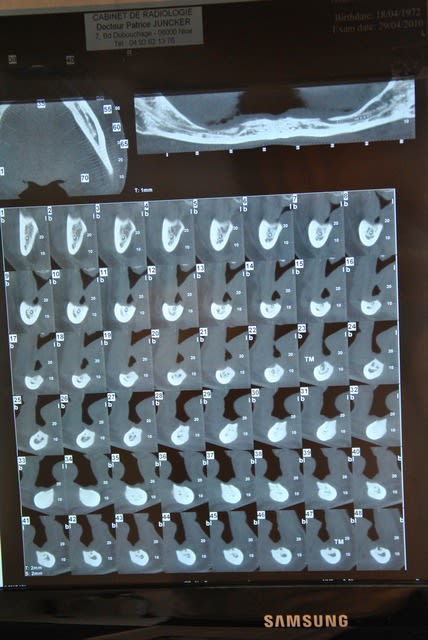

Mais comme son amie me fait une bonne pub elle se decide à passer son scanner et voila le resultat.

au maxillaire sans greffe d'apposition osseuse je ne vois pas comment faire quelque chose de correct,et à la mandibule à part deux implant symphisaire et locator je sais ps comment faire. J'aurai bien aimé un all on 4 pour eviter de trop appuyer sur les cretes tres resorbées en posterieur avec nerf quasiment sur la crete,

sous réserves d'un examen complet (scan en dicom pour étude) je pense que c'est un cas similaire à celui de D57:

8 implants maxillaire

et possiblement 5+2 mandibulaire

à priori sans greffe (expansion), mais pas sans effort!